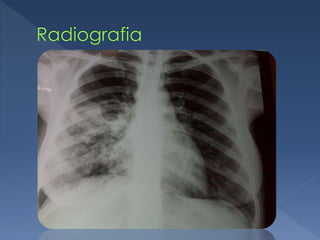

 A tuberculose (TB) é uma doença

infecciosa e transmissível que afeta

prioritariamente os pulmões. A doença é

 A tuberculose(TB) é uma doença infecciosa e transmissível que afeta prioritariamente os pulmões. A doença é curável.  Causada pelo Mycobacterium Tuberculosis.